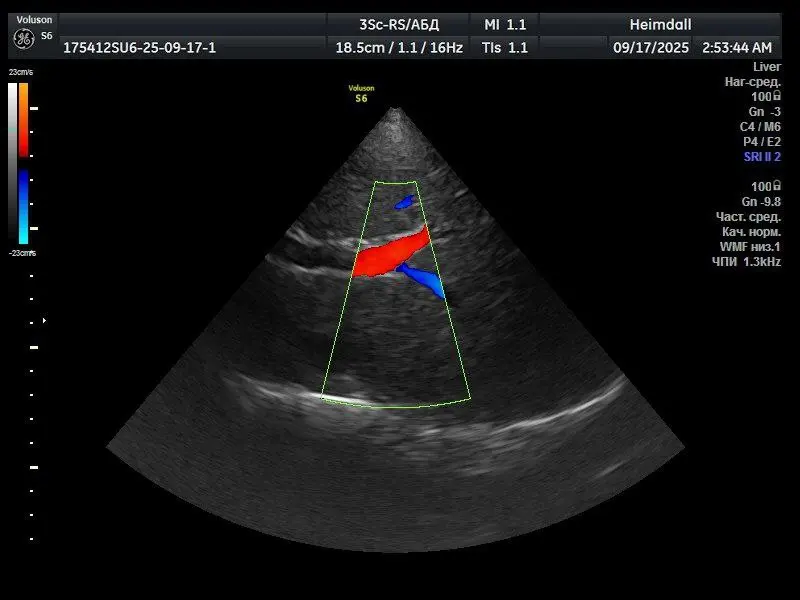

GE 3Sc-RS — фазированный кардиологический ультразвуковой датчик, предназначенный для визуализации сердца и сосудов. Обеспечивает работу в режимах 2D, цветового допплера (C) и импульсно-волнового допплера (PW). Высокая плотность элементов матрицы и фазированная технология требуют стабильной работы всех пьезоэлементов и модулей обработки сигнала. Проблема Пользователь сообщил о полной неработоспособности режимов C и PW. Во всех режимах наблюдались […]